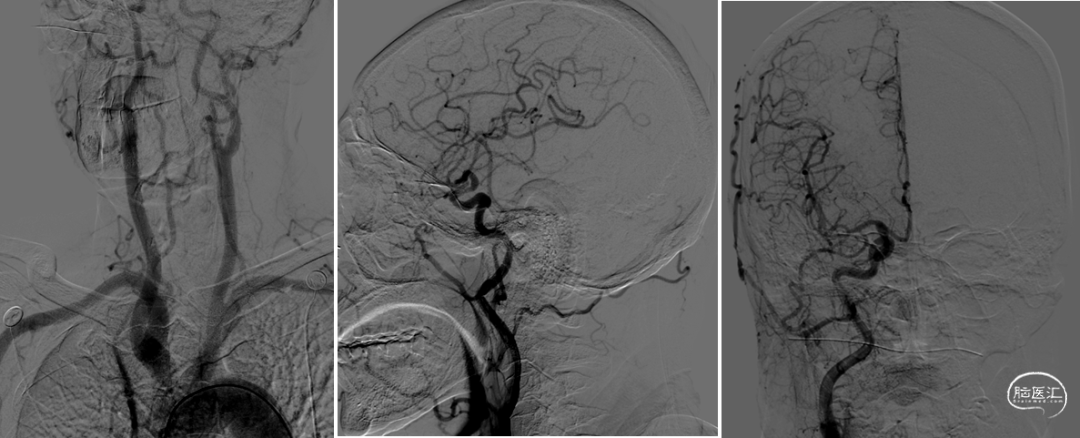

脑血管造影:主动脉弓+右侧颈总动脉造影。

左侧颈总动脉造影。

左侧锁骨下动脉造影。

右侧锁骨下动脉造影。

全麻后,股动脉置入6F血管鞘,6F导引导管配合超滑导丝至右侧锁骨下动脉建立通路,Synchro-14(200cm)微导丝配合4mm×30mm快交球囊定位V1狭窄扩张。

6F导引导管进入V2后,Synchro-14 (200cm)微导丝配合Gateway 2.5mm×9mm球囊先后进行基底动脉、椎动脉V4段狭窄扩张。

撤出球囊后,Synchro-14(200cm)微导丝配合XT-27至基底动脉远端,从远至近分别置入Neuroform EZ 3mm×15mm及Neuroform EZ 3.5mm×20mm支架。

最后保留微导丝在椎动脉内,将导引导管退至锁骨下动脉后,送入5mm×19mm球扩式支架并释放。